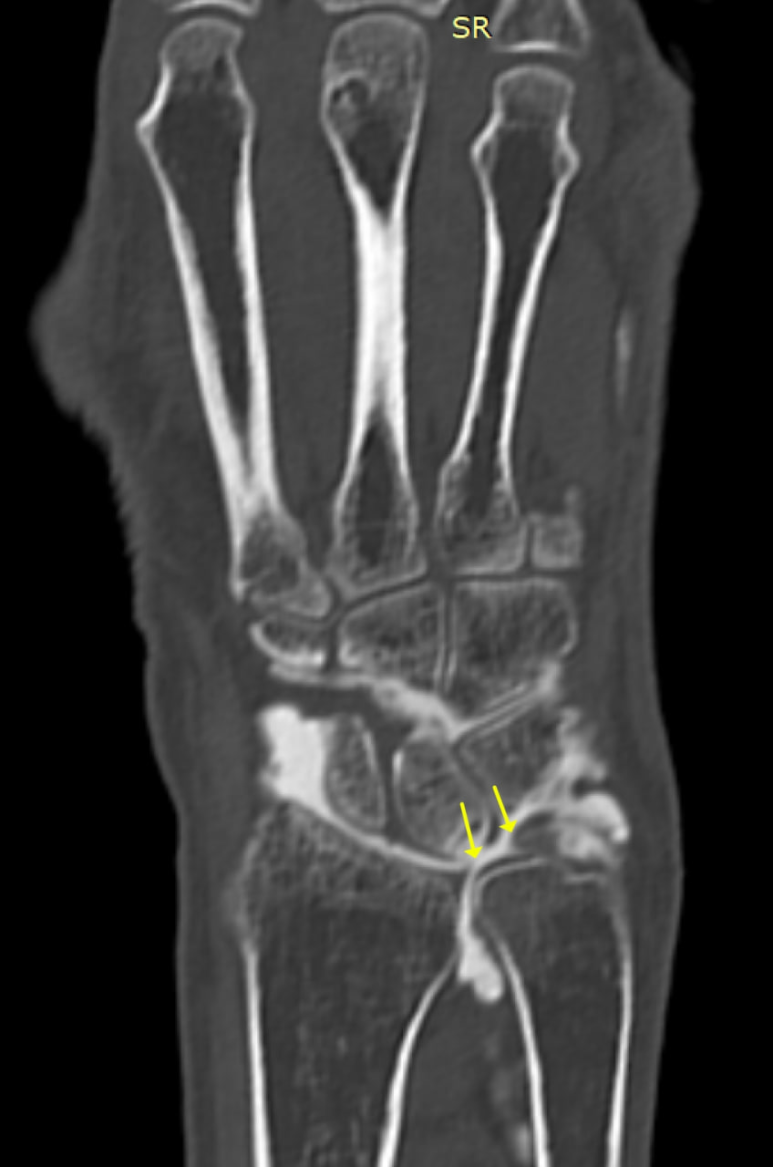

TFCC 파열을 진단하는

가장 확실한 골든 스탠다드는

관절에 조영제를 직접 주사한 뒤 검사하는

**'MRI 관절 조영술'입니다.

관절 주머니에 밝은 조영제를 넣으면

주변 구조물이 훨씬 선명하게 보이거든요.

노란색 화살표 친

**'삼각섬유연골'은

**'손목 관절'과

'원위요척관절' 사이에 있는데**

연골이 파열되면

그 틈으로 조영제가 새어 나가는 것을

직접 눈으로 확인할 수 있습니다.

@ https://doi.org/10.1186/s12891-020-03321-2

원래는 TFC로 막혀있어야 할

손목 관절과 원위요척관절이

파열로 틈이 생기면서

서로 연결되는 것이죠.